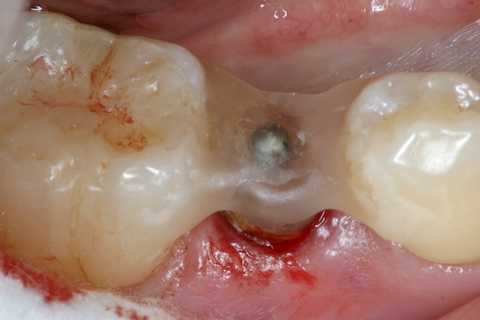

今日の抜歯再植術シリーズ35.3 2025.11.19